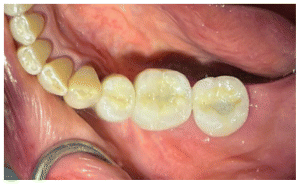

Due to the angulation of the crowns individual milled abutments were fabricated to correct the angulation and achieve a better occlusion with porcelain-fused-to-metal crowns. (Figures 31, 32).

The first premolar due to the inclination had to be milled and a cemente Crown was used, the mollars were milled and scre retained (Figure 33).

The abutments were torqued to 30 Newtons. The premolar crown was cemented with Premier implant cement, and the screw access channels of the molar crowns were filled with resin (Figs. 34, 35).